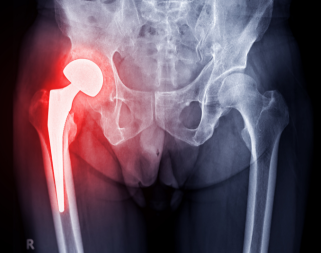

Dr. Turab Syed is a fellowship-trained orthopaedic surgeon who specialises in elective lower limb surgery and general trauma. He has fellowship training in Foot and Ankle surgery, Hip and Knee Arthroplasty, Sports Surgery as well as Trauma.

Mr. Syed offers comprehensive foot and ankle care including the most advanced and effective surgical and nonsurgical interventions. He also performs state-of-the art minimally invasive surgery and hip and knee replacement surgery.